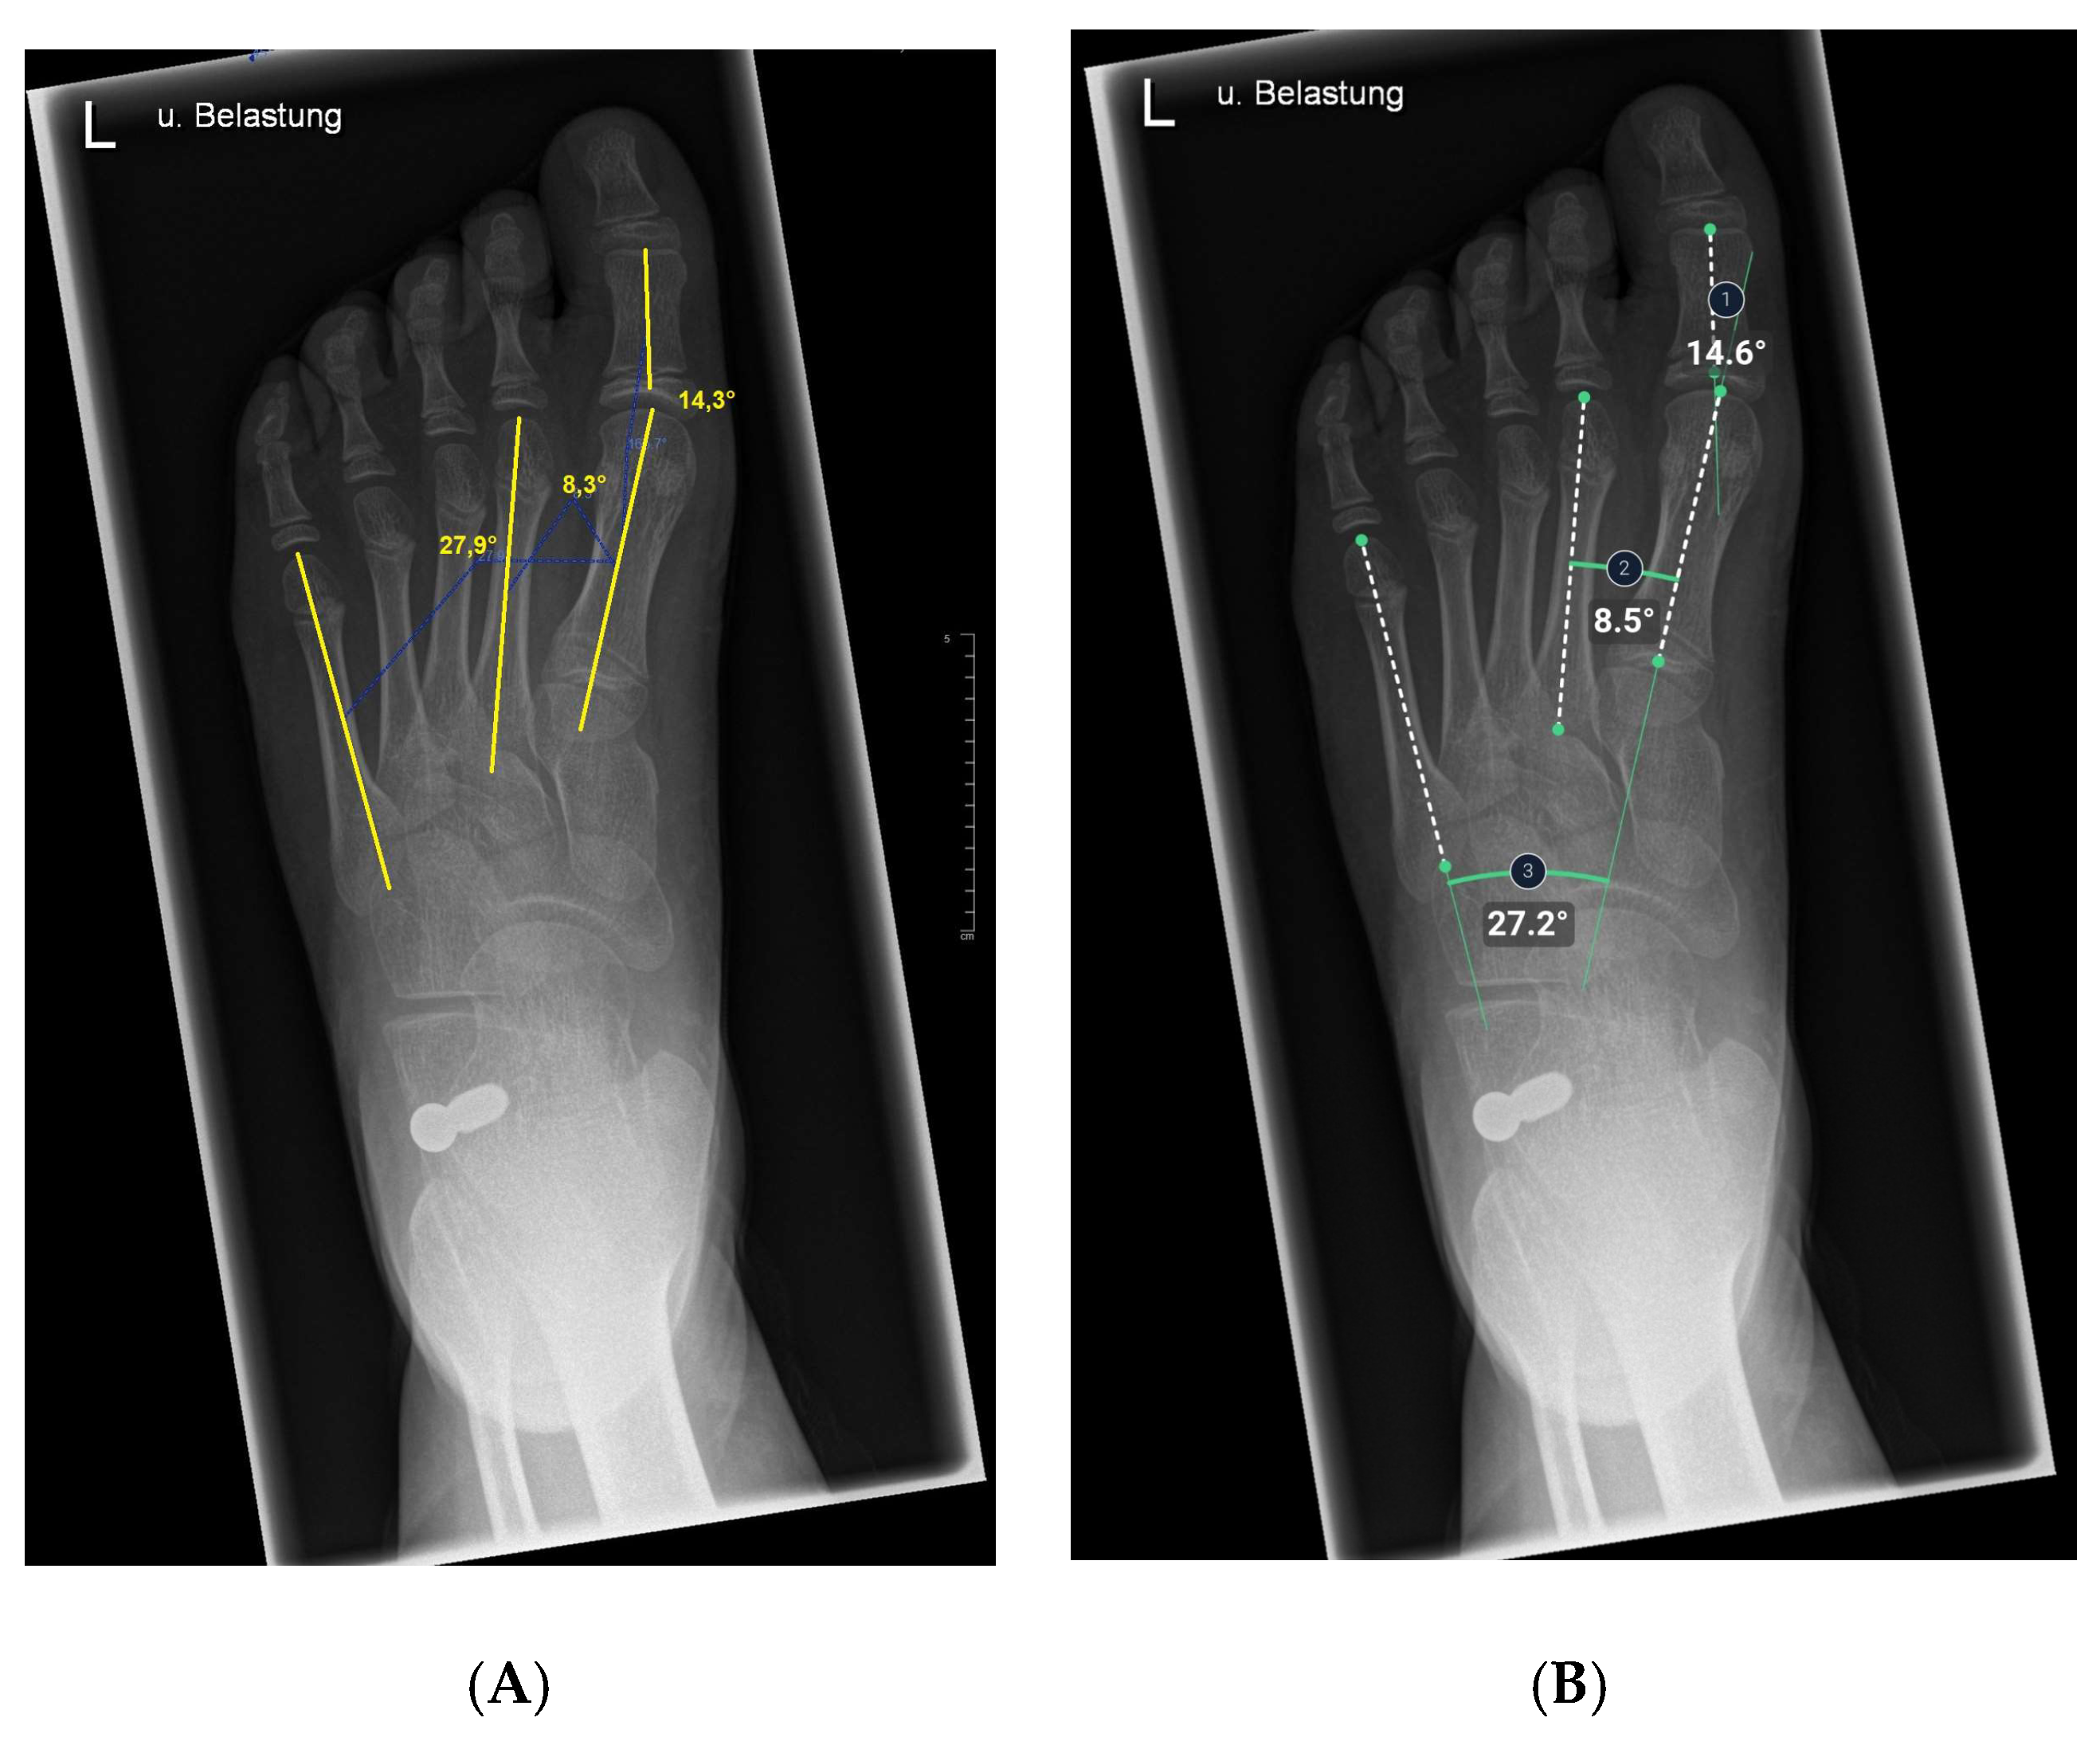

2.5. Anatomic Definitions

The hallux valgus angle is determined by the axis of the first metatarsal bone that of the proximal phalanx [23,32].

Having intersected the axis of the first metatarsal bone with the axis of the second metatarsal bone, the 1st-2nd metatarsal angle was obtained [23,32].

The intersection of the axes of the 1st metatarsal and 5th metatarsal resulted in the third and last angle examined, the 1st-5th metatarsal angle [23].

Figure 3. Illustration of hallux valgus angle, 1st–2nd metatarsal angle, and 1st–5th metatarsal angle measurements on x-ray images in the dorsoplantar plane. (A) Manual measurement exemplary. The same x-ray image was processed by the AI. (B) shows the angles calculated by AI.